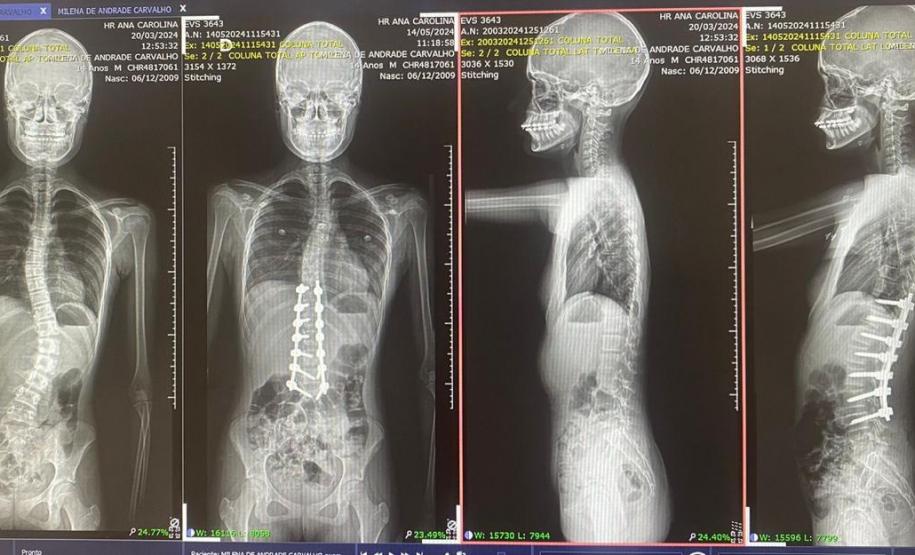

Aos 14 anos, a adolescente Milena de Andrade Carvalho, moradora de Guaratuba, no Litoral do Estado, foi diagnosticada com escoliose idiopática. Sem causa definida, esse tipo de escoliose pode surgir a partir dos quatro anos até a adolescência e ocorre durante o estirão de crescimento. Quando a condição da curvatura ultrapassa os 40 graus, a escoliose se torna progressiva e o paciente continua entortando. Essa condição ocorre com maior frequência em meninas e é muito importante que os pais estejam atentos a qualquer sinal do problema.

“Descobrimos a escoliose por acaso, nunca tínhamos percebido a deformidade, até que um dia ao amarrar meu biquíni, minha mãe observou que eu estava com a coluna torta e ao passar a mão percebeu a curvatura. Decidimos então procurar atendimento médico e tive o diagnóstico da doença já com 50 graus de curvatura e indicação imediata de cirurgia”, contou a adolescente.